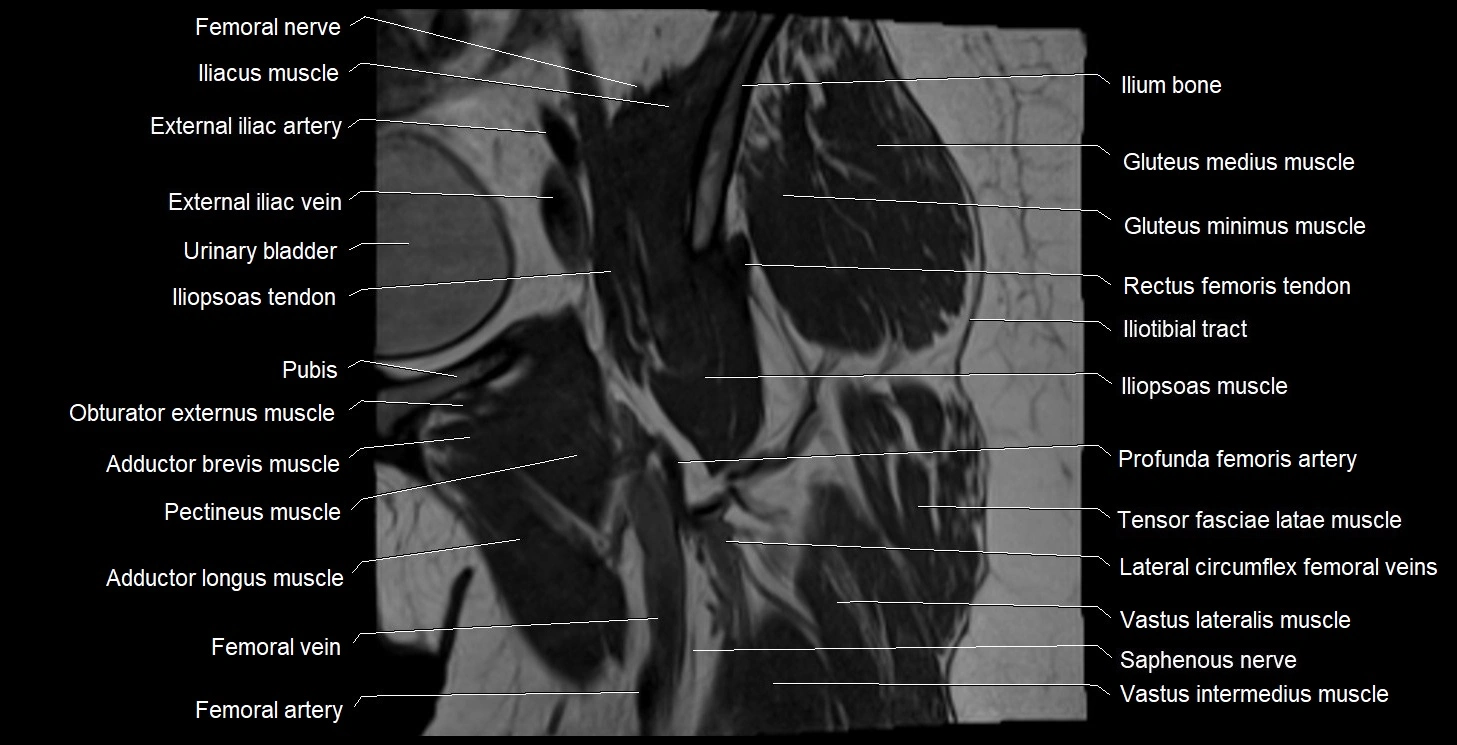

- External iliac artery

- External iliac vein

- Femoral artery

- Femoral nerve

- Femoral vein

- Gluteus medius muscle

- Gluteus minimus muscle

- Iliopsoas muscle

- Iliopsoas tendon

- Iliotibial tract

- Ilium bone

- Lateral circumflex femoral veins

- Lateral femoral cutaneous nerve

- Obturator externus muscle

- Pectineus muscle

- Pubic bone

- Rectus femoris muscle

- Rectus femoris tendon (Proximal tendon of rectus femoris)

- Saphenous nerve

- Tensor fasciae latae muscle

- Urinary bladder

- Vastus intermedius muscle

- Vastus lateralis muscle